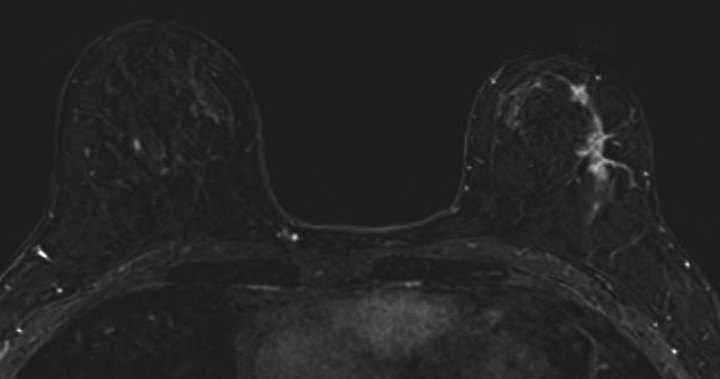

الحالة الثانية: اتضح وجود كتلة كبيرة في الصدر الأيمن بعد الفحص وعمل خزعة تحت الأشعة التلفزيونية ثم رنين مغناطيسي للصدر يوضح انتشارها. تم علاج المريضة وعمل رنين مغناطيسي يوضح صغر الكتلة بشكل كبير جدا ثم تم استئصال الثدي الأيسر بشكل كامل وترميمه جراحيا.